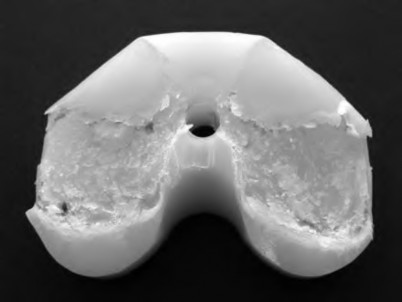

Question 4:

A 55-year-old woman feels a 'pop' in the back of her knee while squatting. An MRI is shown: A posterior horn medial meniscus root tear is identified. Biomechanically, a complete medial meniscus posterior root tear alters contact pressures to a degree equivalent to which of the following?

Correct Answer: Total meniscectomy

Explanation:

A complete posterior root tear of the medial meniscus leads to a complete loss of hoop stresses, resulting in meniscal extrusion. Biomechanically, this alters peak tibiofemoral contact pressures and reduces contact area to a degree equivalent to a total meniscectomy, leading to rapid articular cartilage degeneration.